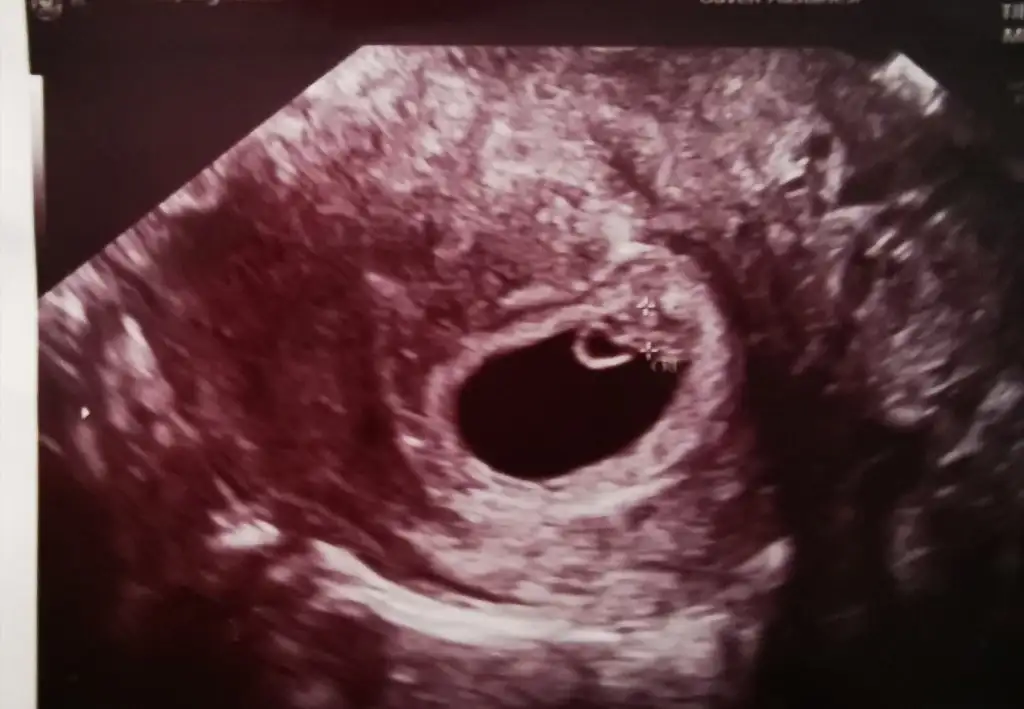

Herkese merhaba kızlar, sağlıcakla bebişlerimize kavuşalım inşallah. T tulperde Ramzi teorisi tahminlerinde başarını görünce bir ricada da ben bulunayım istedim cinsiyet her ne kadar önemli olmasa da insan merak ediyor. 2li testte tahmin alamadık, burada 6 haftalık vajinal ultrason görüntüsü, bana da bir tahmin de bulunabilir misin?

İçime erkek doğdu. Ama sadece bir tahmin tabi :)